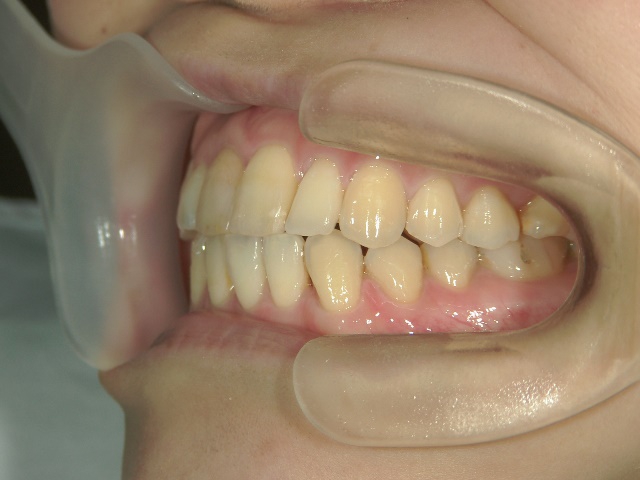

矯正歯科 治療後矯正歯科 プチワイヤー矯正 治療後矯正歯科(プチワイヤー矯正)治療後

矯正歯科 治療後  スペース確保の為、 2番抜歯

no.37_7548_治療後_右.JPGno.37_7548_治療後_正面.JPGno.37_7548_治療後_左.JPG